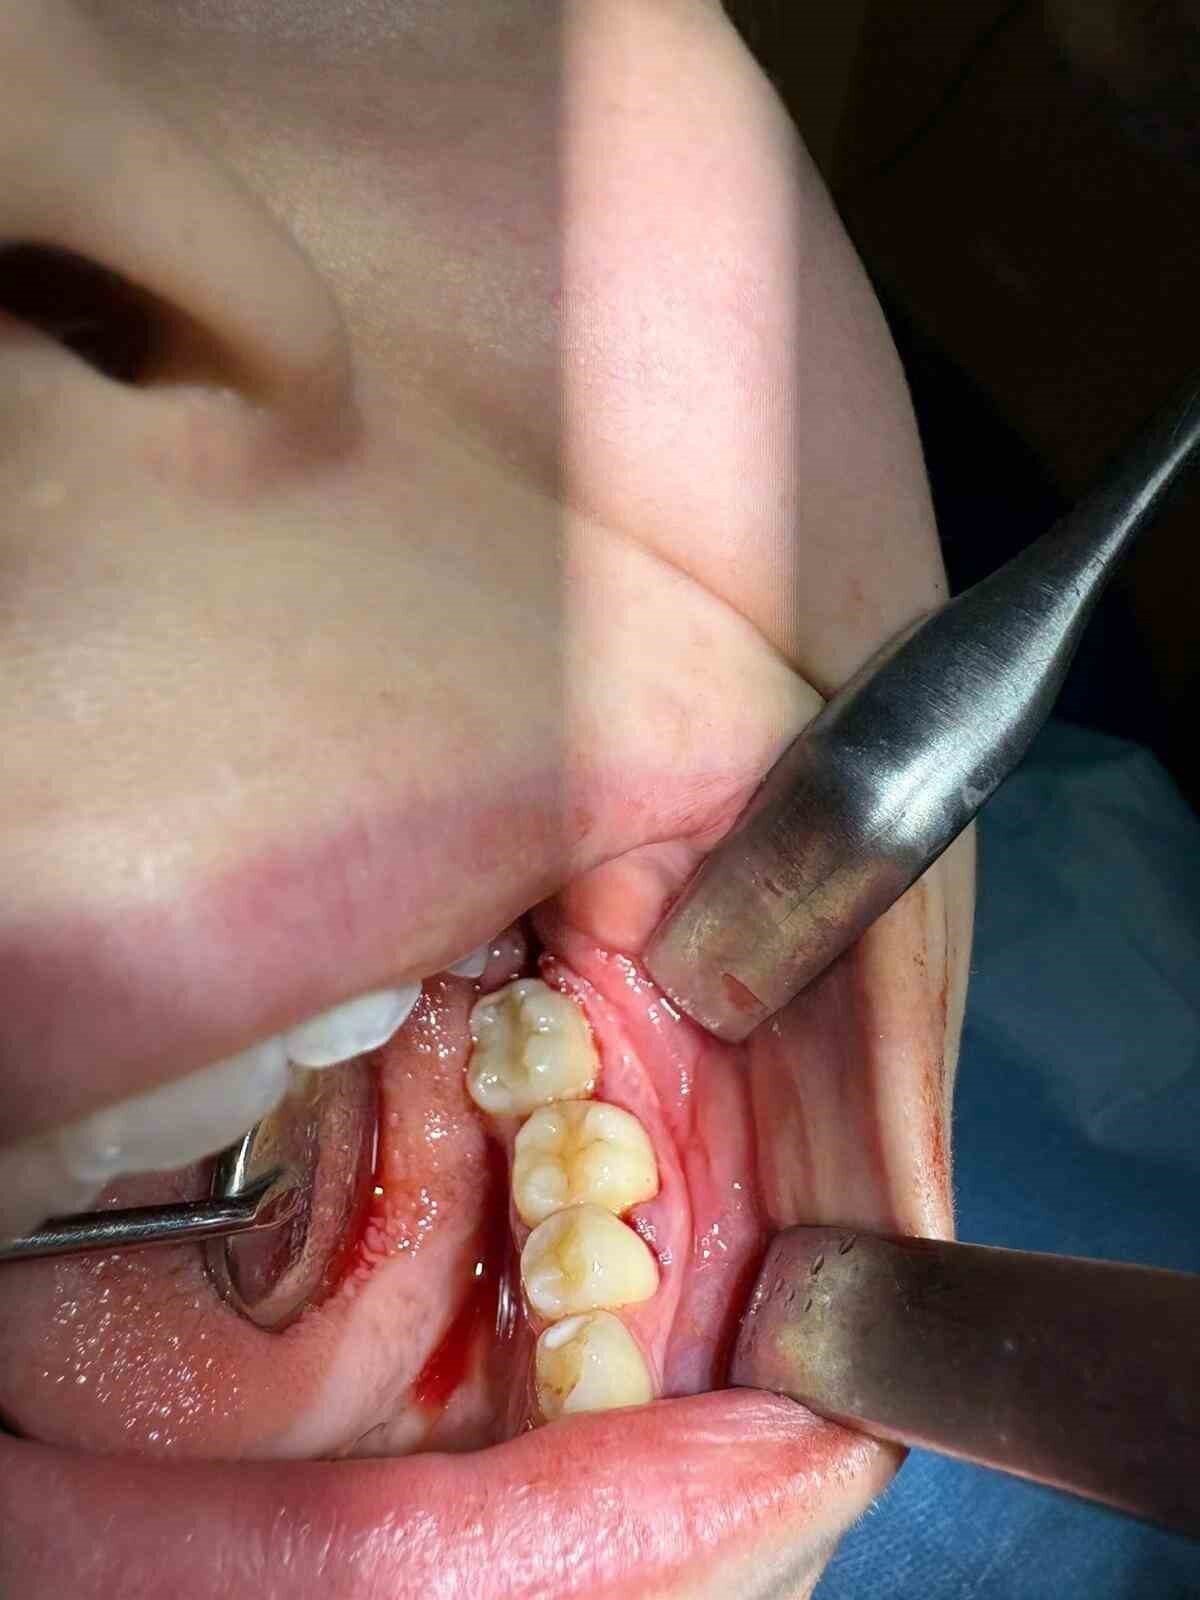

Hastanın daimi azı dişi, ileri düzey çürük nedeniyle çekilmişti. Yaşı itibarıyla çene gelişimi henüz devam eden hastada, geleneksel implant tedavisi uygun bulunmadı. Uzman ekip, hastanın ağız içinde gömülü durumda bulunan yirmi yaş dişini cerrahi bir işlemle çıkararak, çekilen dişin yerine nakil etti.

Operasyon sürecinde, dişin yerinde sağlıklı bir şekilde tutunabilmesi için hastanın kendi kanından elde edilen PRF (Platelet Rich Fibrin) biyomateryali, diş yuvasına yerleştirildi. Bu doğal yöntem, doku iyileşmesini hızlandırdığı gibi hücre yenilenmesi üzerindeki olumlu etkisi ile dikkat çekiyor. Hastanın kendi dişinin kullanılması, görünüm, uyum ve fonksiyon açısından önemli avantajlar sunarken, vücut tarafından kabul edilme oranı yüksek olduğundan, uzun vadeli başarı olasılığı da artıyor.